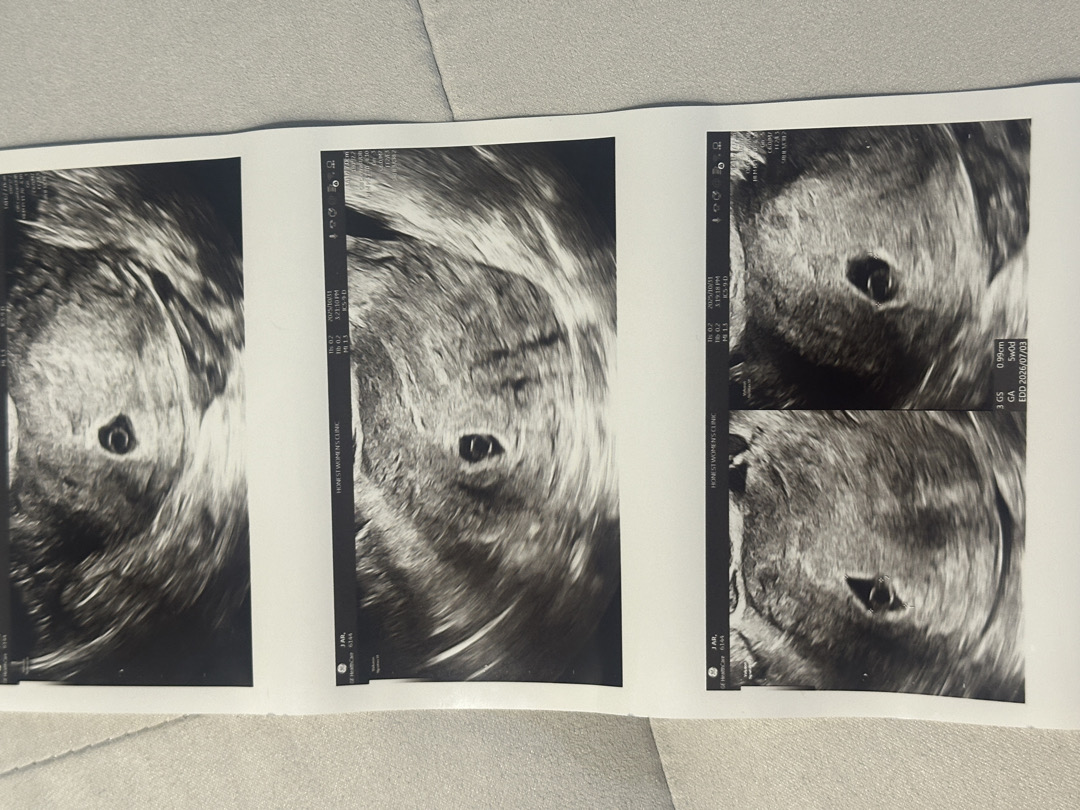

다낭성이 있어서 배란유도제먹고 임신 시도했습니다. 9월 17일 막생 9월 26일 난포터뜨리는주사 10월 12일 임테기 두줄 확인 10월 13일 병원에서 피검사 146 확인 10월 24일 아기집 0.55cm 확인 초음파상 4주3일 10월 27일 아기집 0.74cm 난황 확인 초음파상 4주 5일 10월 28일 아기집 0.85cm 난황 확인 초음파상 4주 6일 10월 31일 아기집 0.99cm 난황 확인 아기 없음초음파상 5주 0일 병원에서 피검사 수치 뜬 날로 주수는 6주로 확인되는데 아기집이 작다, 아기심장소리가 들릴 때인데 안들린다, 아기집 성장속도가 느려서 다음주까지 경과보고 아기도 안보이면 계류유산 염두해야할 것같다고 하네요… 병원 혼자갔다 오는 길 한바탕 쏟아지게 울고, 남편이 그래도 확정이 아니니 아기집으로 갈 수분 그만 쏟고 남은 일주일 최선을 다해보자고 해서 다시 힘을 얻고 이렇게 글 올려요.. 우리 아기 괜찮겠죠?? 혹시 저와 비슷한 상황이셨던 분 계실까요??ㅠㅠ